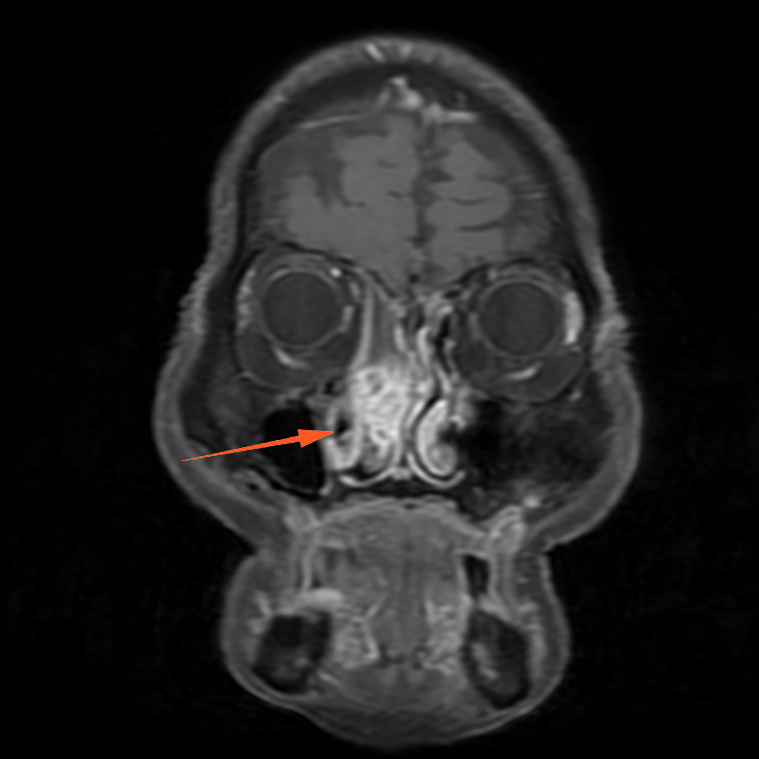

进一步增强MR显示:鼻腔右侧异常信号影,T1等信号,T2等高信号,DWI高信号,增强后周边强化为主。

蒋主任仔细阅读影像学图像,该患者的肿物在T2相有 “脑回征”,但又不典型,鼻窦骨质也没有明显的增生,肿物已经占满整个右侧额窦窦腔,好在患者额窦气化尚可,肿物未越过瞳孔中线,要彻底清除肿物,需要打开额窦,将窦内软组织完全清理干净并磨除基底部部分骨质再烧灼。